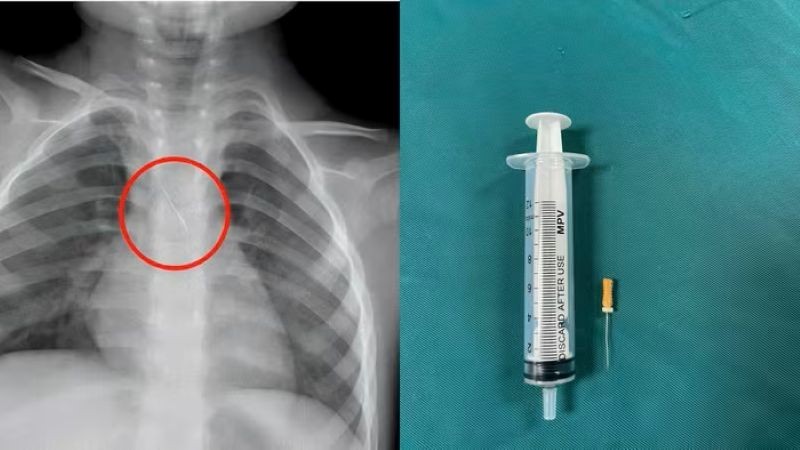

Dị vật trong đường thở của bệnh nhi. (Ảnh: Bệnh viện Đa khoa tỉnh Quảng Trị)

Trước đó, bệnh viện tiếp nhận bệnh nhi N.Q.T.Đ, 3 tuổi, trú tại xã Cửa Việt, Quảng Trị trong tình trạng ho nhiều, ho sặc. Kết quả chụp phim cho thấy 1 dị vật kim loại dài khoảng 22mm nằm ở góc carina (vị trí chia đôi khí quản) đe dọa gây tắc nghẽn đường thở.

Ngay lập tức, các bác sĩ hội chẩn liên khoa và quyết định nội soi phế quản cấp cứu. Dị vật được phát hiện có một đầu nhọn cắm vào 1/3 dưới khí quản, đầu còn lại nằm trong phế quản gốc trái.